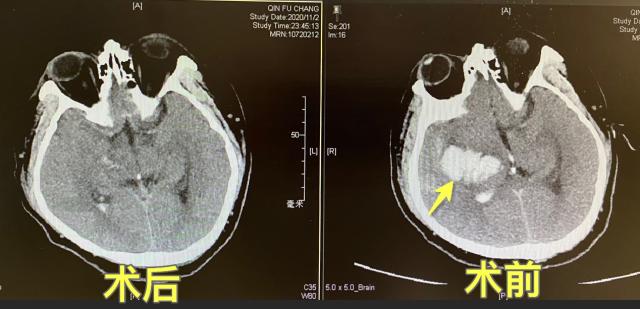

入院时,老秦已意识昏迷,神经外科二线医师章薇快速赶到急诊评估病情,患者血压高,头颅CT显示右侧基底节区脑出血,量约30毫升,初步诊断为高血压导致的脑出血。次日,经过充分的术前准备,神经外科团队为老秦成功地实施了神经内镜下的微创脑内血肿清除术。

该手术由章薇医师主刀,在神经导航下,为患者进行精准备皮;在神经内镜的引导下,将颅内血肿清除,并探查血肿腔内可疑的出血点,完善止血流程,尽可能降低再次出血的风险。相对于常规开颅手术,该微创手术全程仅耗时45分钟,失血量为10毫升。术后复查的头颅CT提示,患者颅内的血肿清除彻底。

术后头颅CT复查结果提示血肿清除彻底